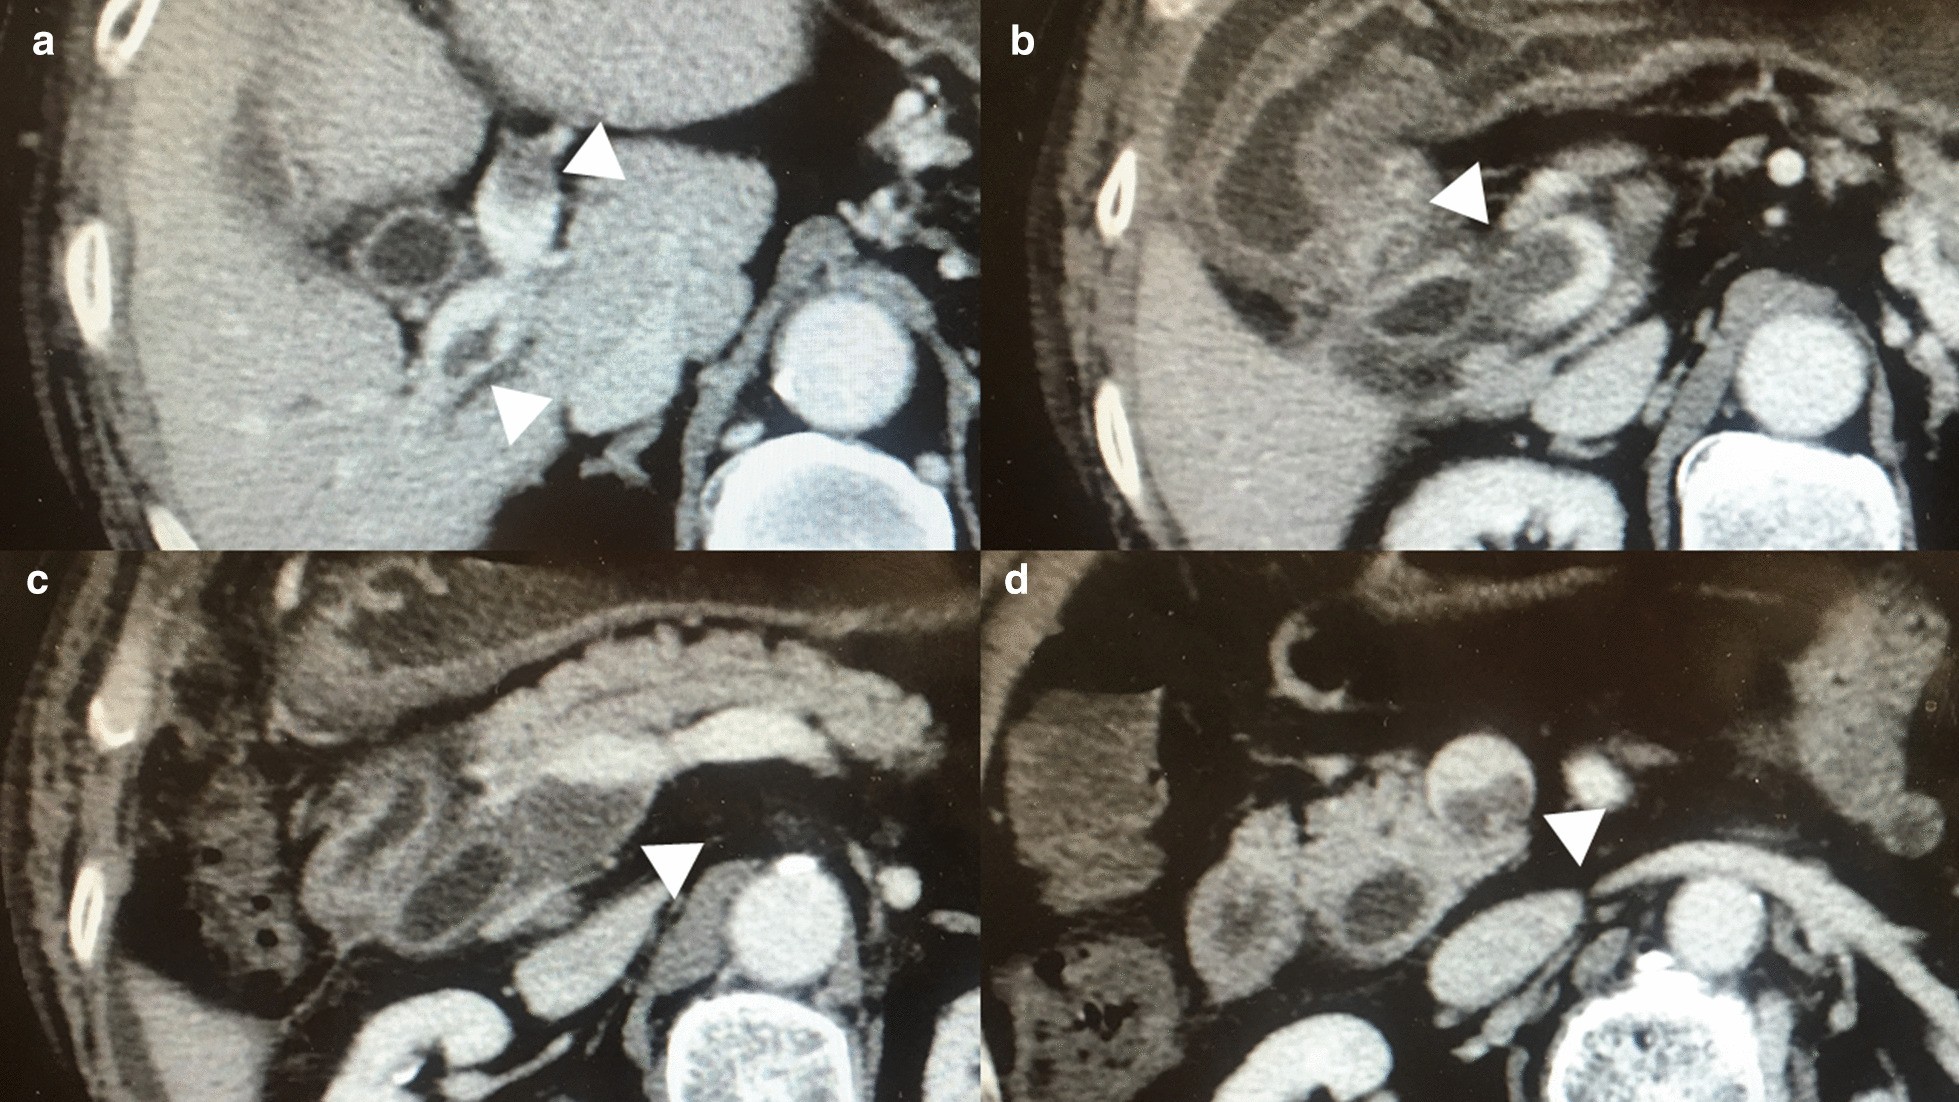

Fig. 3

Findings of the portal vein thrombosis on postoperative day 8. Exacerbation of the portal vein thrombosis (PVT) (White arrowheads) was noticed with the findings of contrast-enhanced computed tomography taken on postoperative day 7. The PVT extended cephalically beyond the bifurcation of the right and left portal veins (a). The stenosis caused by the PVT was deteriorated either in the portal trunk (b) or in the confluence of the superior mesenteric vein and the splenic vein (c). Furthermore, the PVT extended much more caudally compared to the preoperative period (d). (CHD common hepatic duct; and CBD common bile duct)